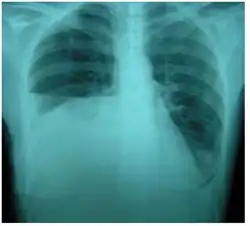

| Right sided pleural effusion caused by urinothorax | |

Urinothorax (pl. urinothoraces) is defined as urine in the fluid-filled cavity that surrounds the lungs.[1] It is usually caused by obstructive uropathy. It is mainly diagnosed by analyzing the pleural fluid. Treatment involves treating the underlying condition, which typically results in resolution of the urinothorax. It is an extremely rare cause of pleural effusion.[2]